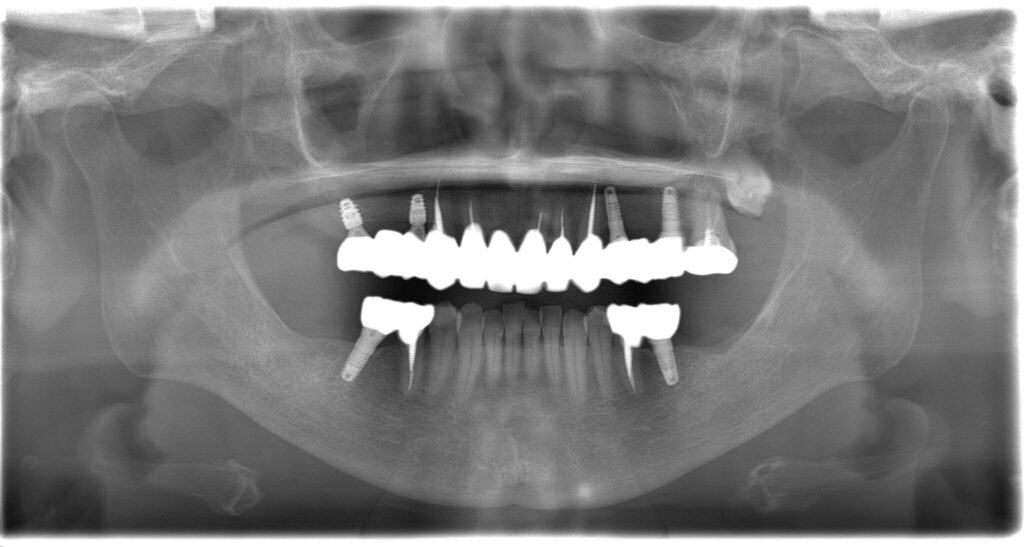

| 治療内容 | インプラント埋入(右上4・6,左上4・6,右下6,左下6) ジルコニアBr(右上3―左上3) ジルコニア(右下5,左下5) |

インプラント 1年5ヶ月/13回 ジルコニアBr、ジルコニアクラウン 3ヶ月/10回 |